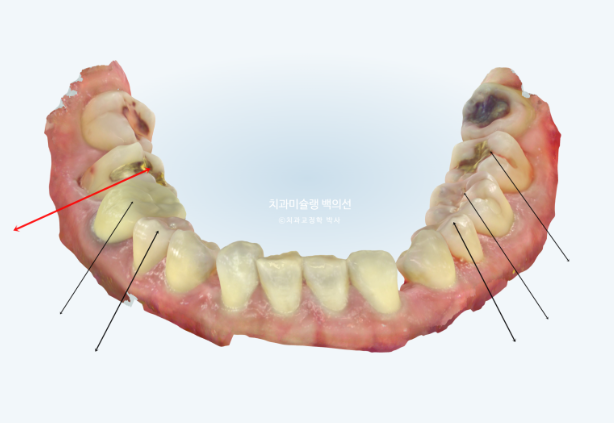

사진에 보이는 구멍은 앞니가 없어 송곳니가 앞니 자리로 이동하고 송곳니와 작은어금니 사이 공간이 벌어져 있습니다.

송곳니가 없는 것 처럼 보이지만 사실은 앞니 2개가 선천적으로 없는 상태입니다.

빨간색 치축으로 표시한 치아가 쓰러진 치아입니다.

이 치아는 씹는데 중요한 역할을 하는 치아이므로 반드시 세워주는 것이 좋습니다.

그러려면 쓰러진 큰어금니 바로 뒤 썩은 사랑니는 빼주는 것이 좋습니다